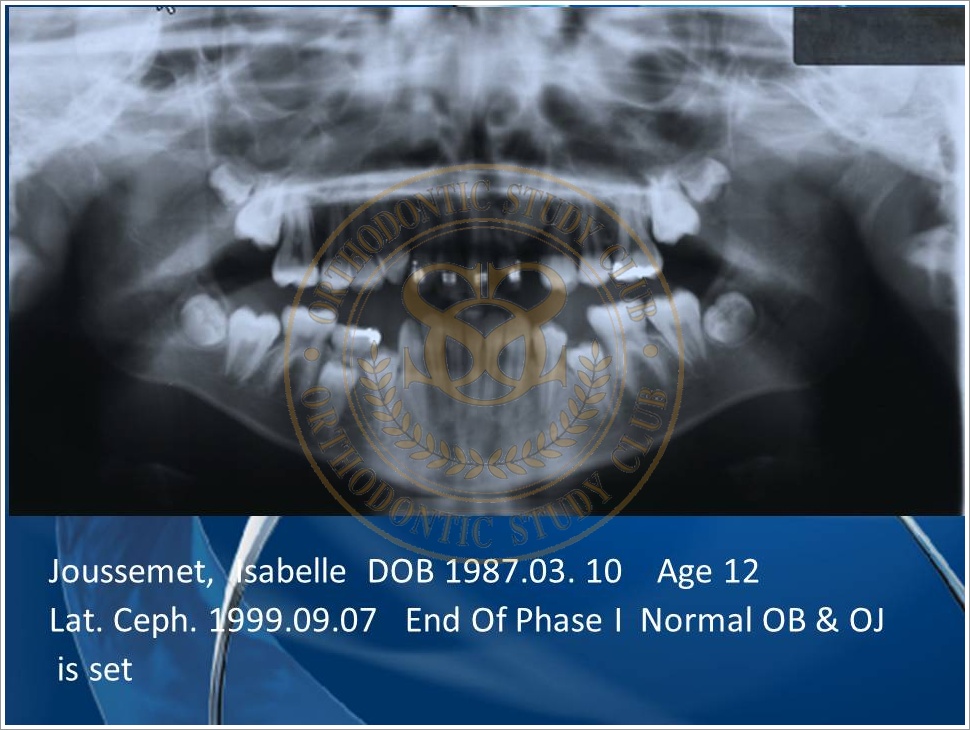

Treatment of Pseudo Class III (Class I Molar Relationship) and management of the embedded maxillary canine (Pt. Miss J.I.)